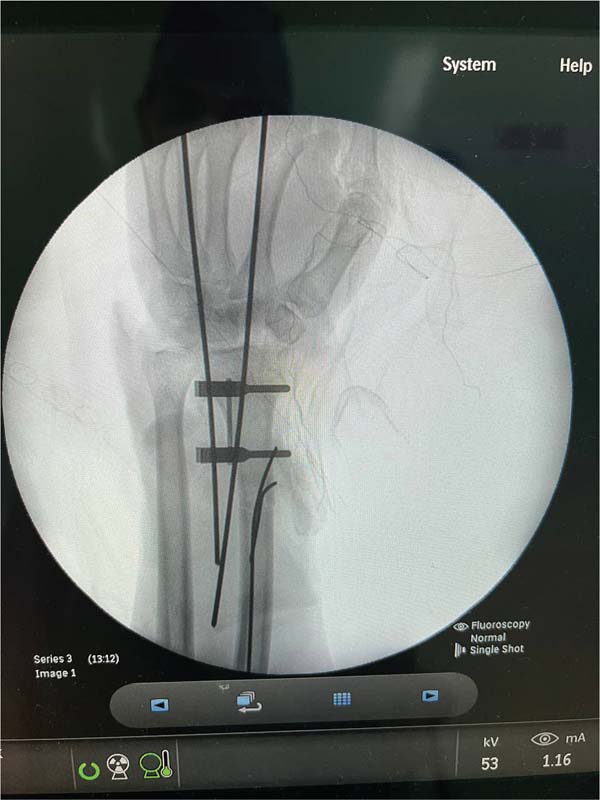

Fig. 4 - Fixação óssea do rádio e artrodese do punho.

Após medidas iniciais de acordo com o protocolo Advanced Trauma Life Support (ATLS), foram realizados os seguintes tempos cirúrgicos: dissecção de cotos vasculares com identificação de artéria radial e ulnar, e nervo ulnar e mediano; heparinização dos vasos sanguíneos da extremidade amputada; fixação óssea do rádio e bloqueio do punho com fios de Kirschner; anastomoses microvasculares primárias da artéria radial e ulnar, assim como 3 veias dorsais; sutura de nervos mediano e ulnar com uso de microscópio; finalizando com tenorrafia em bloco dos flexores e enxertia de pele sobre ferimento devido a perda de substância (►Figs. 4-7).4